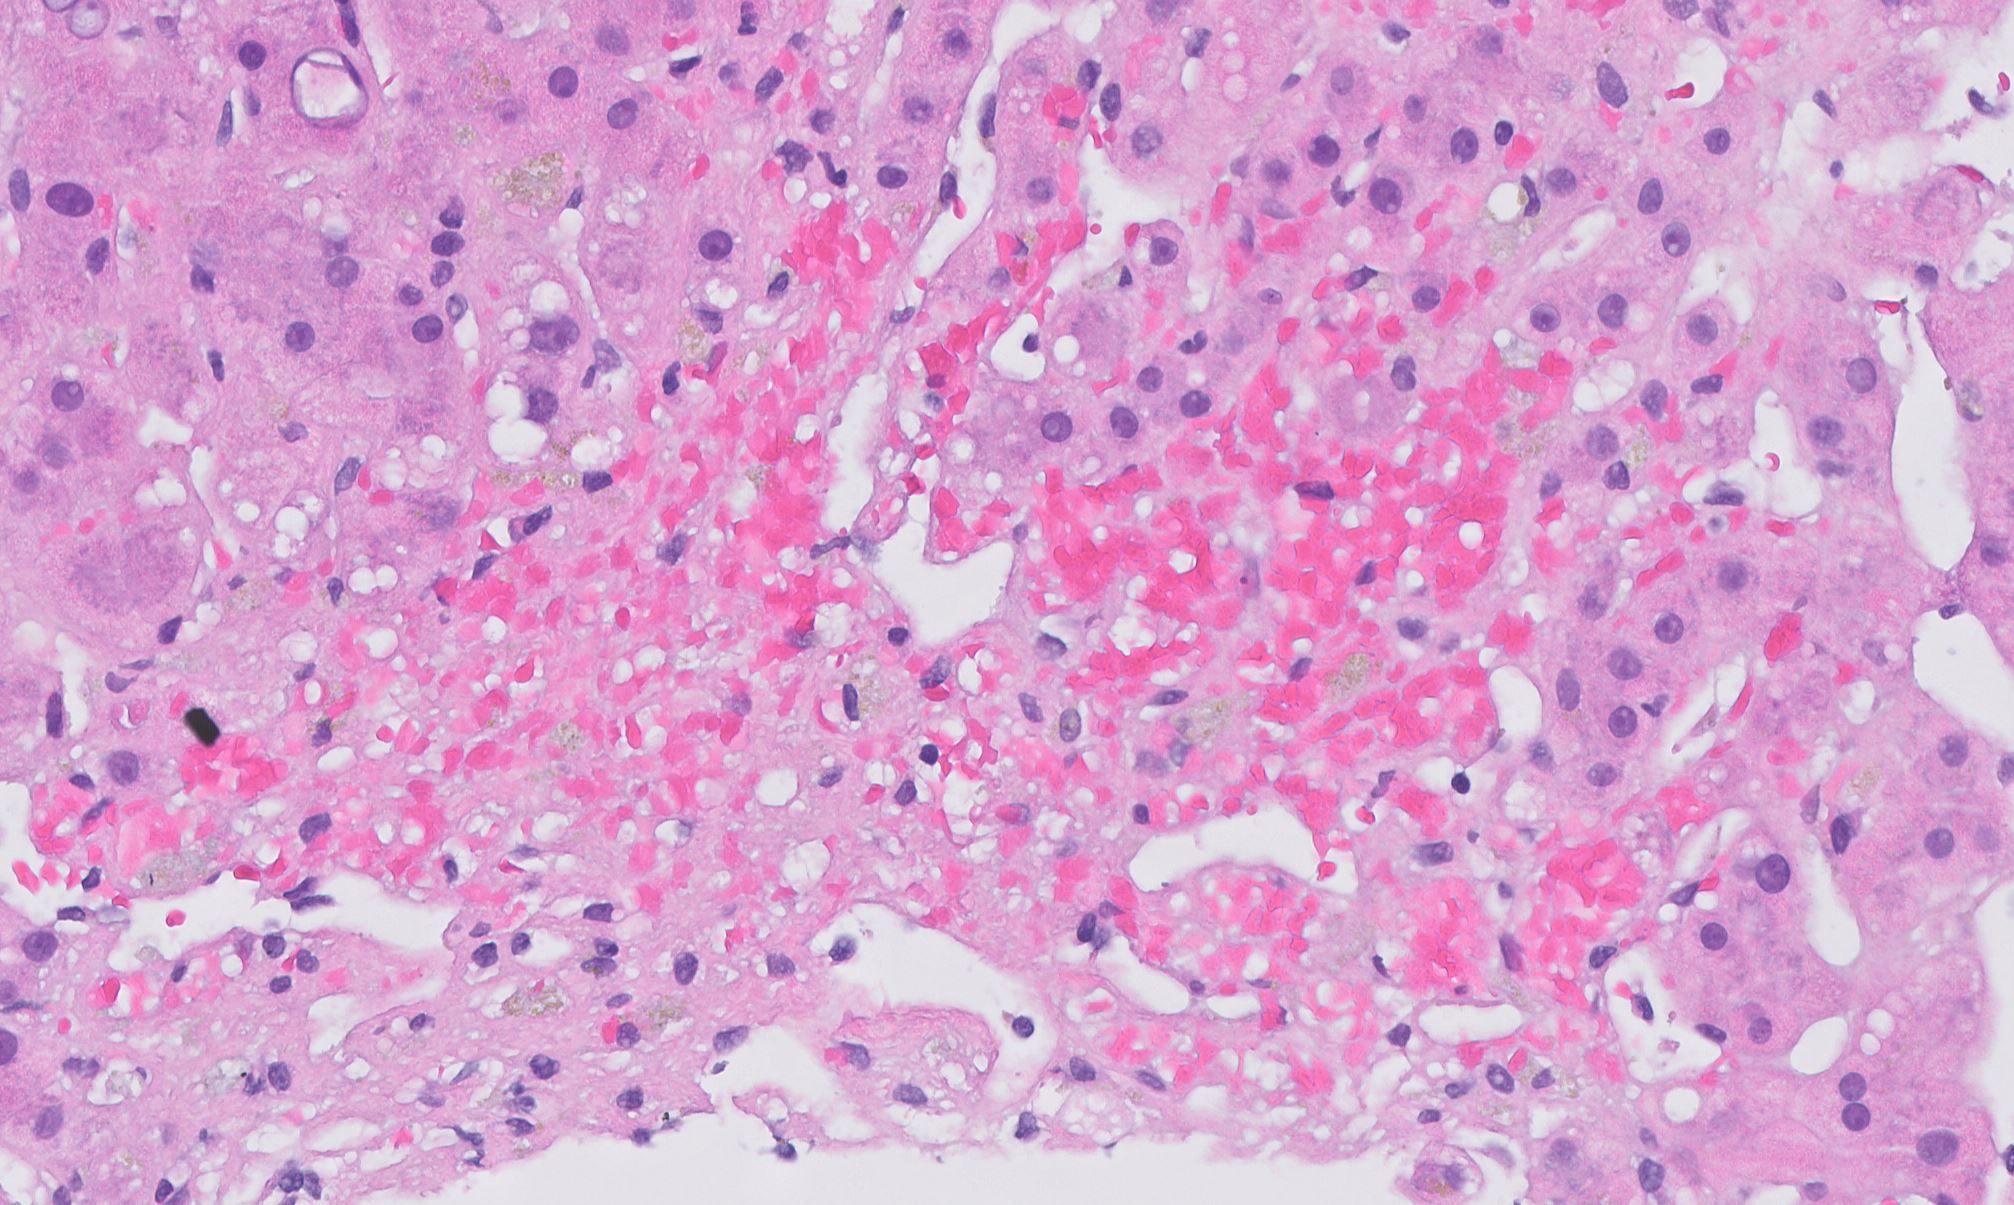

Nutmeg Liver Histology . grossly, the congested liver has been characterized as a “nutmeg liver,” 12 with dark centrilobular zones reflecting. This 47 year old man, a known sufferer from chronic rheumatic valvulitis, was admitted in. microscopically, the nutmeg pattern results from passive congestion around the central veins , as seen here. nutmeg liver is a term for the appearance of liver in chronic venous congestion, which resembles the speckled nutmeg kernel. Here is an example of a nutmeg liver seen with chronic passive congestion of the liver. a nutmeg liver appearance is due to a perfusion abnormality of the liver usually as result of hepatic venous. cardiac (congestive) hepatopathy and fontan associated liver disease are manifestations of chronic,. The congestive liver explant has been characterized as a “nutmeg liver”, due to the presence of dark.

a nutmeg liver appearance is due to a perfusion abnormality of the liver usually as result of hepatic venous. microscopically, the nutmeg pattern results from passive congestion around the central veins , as seen here. This 47 year old man, a known sufferer from chronic rheumatic valvulitis, was admitted in. grossly, the congested liver has been characterized as a “nutmeg liver,” 12 with dark centrilobular zones reflecting. Here is an example of a nutmeg liver seen with chronic passive congestion of the liver. cardiac (congestive) hepatopathy and fontan associated liver disease are manifestations of chronic,. The congestive liver explant has been characterized as a “nutmeg liver”, due to the presence of dark. nutmeg liver is a term for the appearance of liver in chronic venous congestion, which resembles the speckled nutmeg kernel.